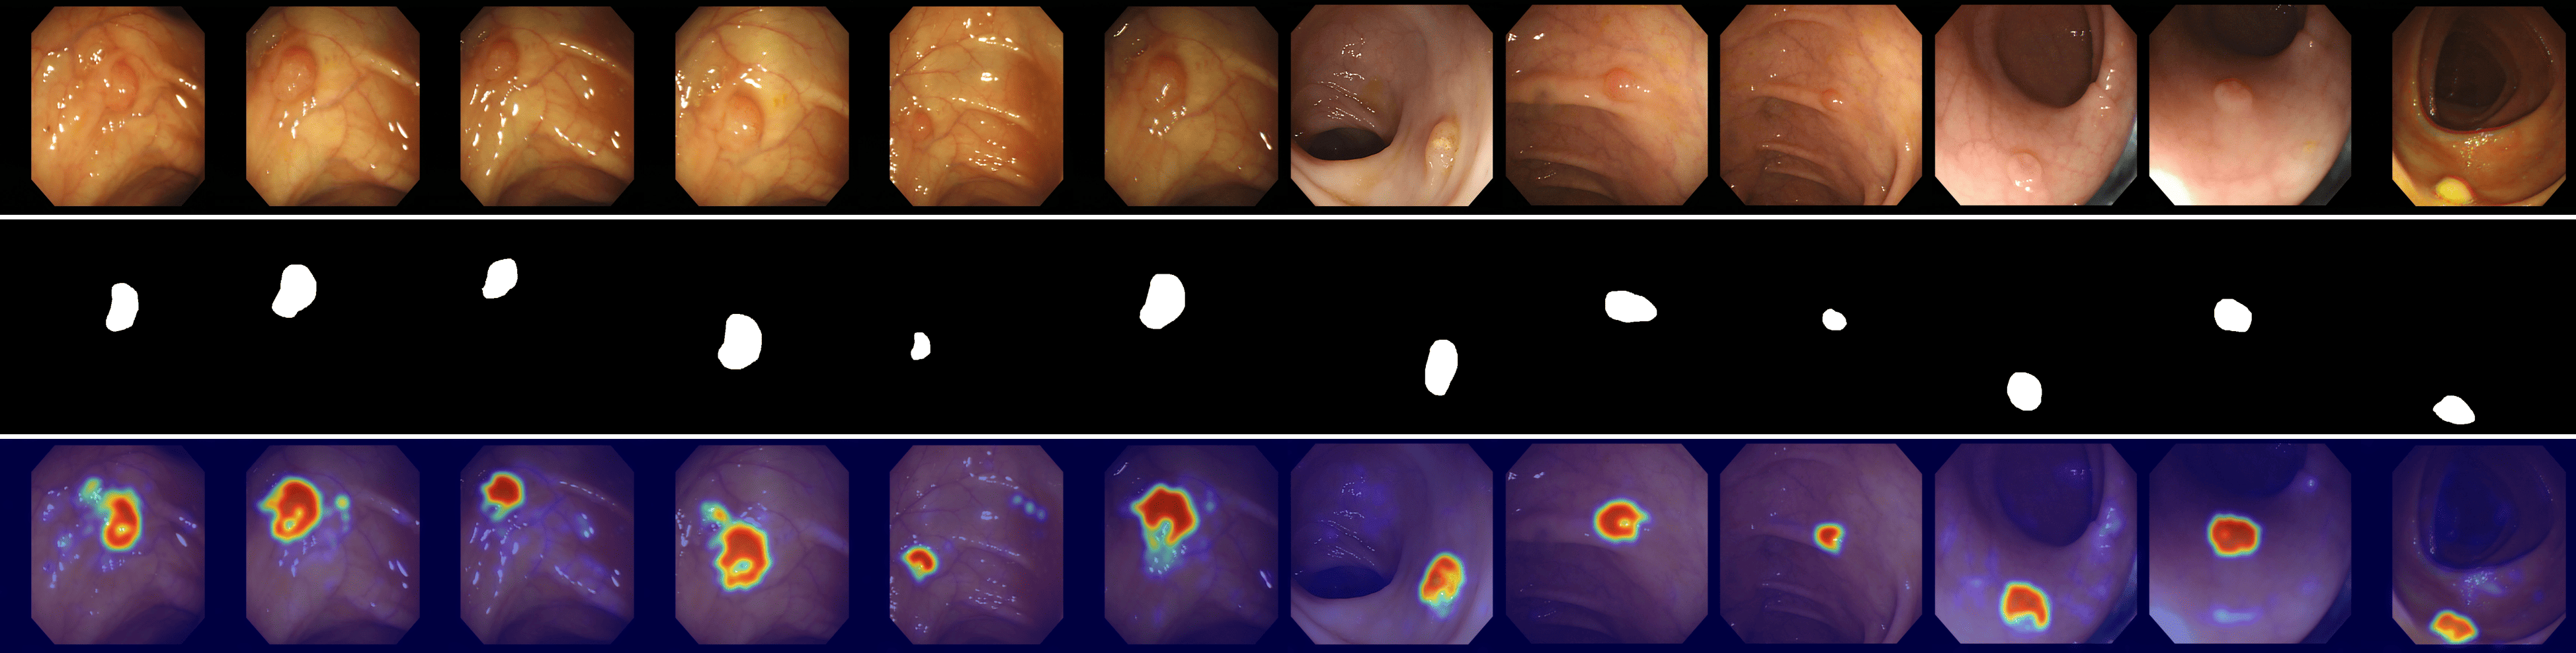

Refer to caption

Figure 3: Comparison of ZSAD results across industrial and medical domains. The first row displays input images from the industrial domain (Hazelnut, Bottle, Metal plate, Leather, Pcb1, Blotchy, and Electrical commutators) and the medical domain (HeadCT, BrainMRI, Endo). The second row presents the ground truth anomaly regions for each image. The remaining rows show the anomaly heatmaps generated by different models: CLIP, WinCLIP, CoOp, AnomalyCLIP, AdaCLIP, and GlocalCLIP.

Qualitative comparison

Fig. 3 shows a comparison of anomaly localization maps across the test domain datasets. In the industrial domain, images containing various defect types, such as hazelnuts, toothbrushes, bottles, metal plates, leather, pcb1, and blotchy. CLIP, CoOp, and WinCLIP struggle to capture fine-grained local anomaly regions. CLIP misinterprets normal and anomalous regions, demonstrating the need for adjustment in ZSAD applications. AnomalyCLIP demonstrated reasonable performance; however, it occasionally failed to capture certain anomaly regions that required a broader global perspective. In the medical domain, visualization results from the HeadCT, BrainMRI, and Endo datasets. CLIP and CoOp faced difficulties detecting anomalies, and while AdaCLIP performed well in certain cases, it failed to fully capture defects in some medical images. The explicit separation of global and local prompts in GlocalCLIP enables it to learn the distribution of normal and anomalous samples independently, and then enhance complementary learning, resolving the trade-off between image- and pixel-level performances caused by a lack of complementary information. Consequently, GlocalCLIP achieves the best ZSAD performance across both industrial and medical domains, demonstrating its generalization capability.